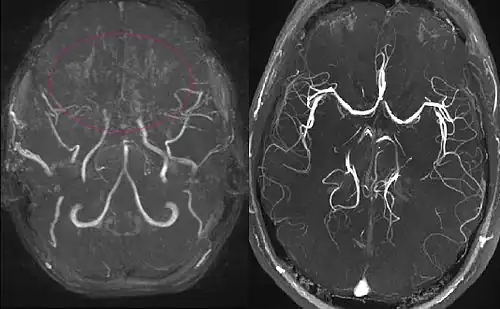

(gauche) Angiographie par résonance magnétique d'une fillette de 11 ans atteinte de la maladie de Moyamoya.

(à droite) Patient en bonne santé, pour comparaison.

L'IRM cérébrale constitue l'examen de choix chez l'enfant, permettant de faire le diagnostic de l'accident vasculaire cérébral et d'en suspecter le mécanisme[9]. l'examen doit être complété par une angiographie cérébrale au cours d'un scanner.